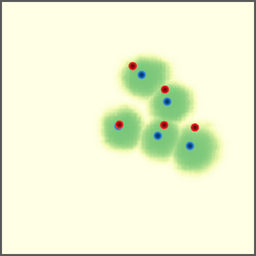

POI Selection. The first step of the proposed approach requires selecting a set of POIs to set up a point-to-point correspondence. In this experiment, we investigate different POI selection strategies. First, we investigate directly using landmarks as the POIs since they usually have strong semantic meaning and can be annotated before the intervention. Second, we also investigate an automatic solution that uses the Harris corners as the POIs to avoid the labor work of annotation. Finally, we try random POI selection.

As shown in Figure 7 (a), we find our approach is prone to overfitting when trained with landmark POIs. This is actually reasonable as each CBCT volume only contains about a dozen of landmarks, which in total is about 3,00030003,000 POIs. Considering the variety of the field of views of our dataset, this is far from enough and leads to the overfitting. For the Harris corners, a few hundreds of POIs are selected from each CBCT volume, and we can see an improvement in performance, but the overfitting still exists (Figure 7 (b)). We find the use of random POIs gives the best performance and generalizes well to unseen data (Figure 7 (c)). This seemly surprising observation is, in fact, reasonable as it forces the model to learn a more general way to extract features at a fine-grained level, instead of memorizing some feature points that may look different when projected from a different view.

Refer to caption

(a) landmark

(b) Harris corner

(c) random

Figure 7: Training and validation losses of different POI selection methods.